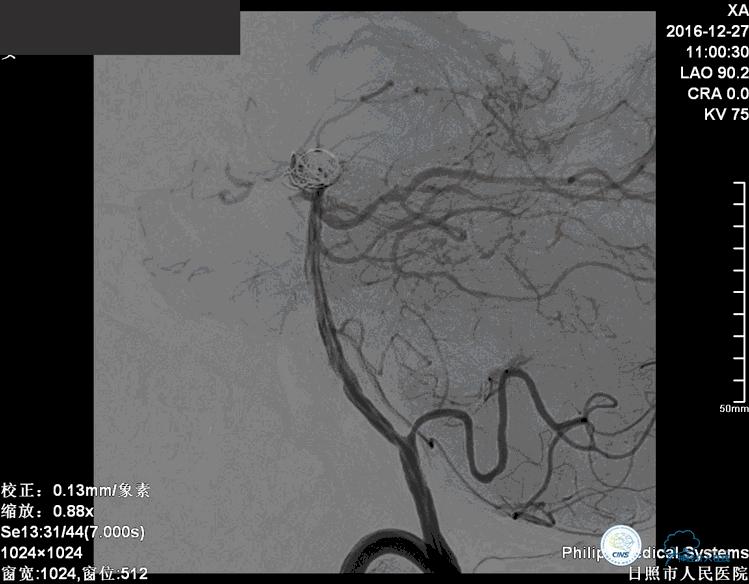

术后患者神志清楚,术后肢体运动较术前未见明显异常。

这个动脉瘤是一个宽颈动脉瘤,动脉瘤的瘤颈和双侧的大脑后动脉关系比较密切。在进行栓塞治疗的时候要避免弹簧圈对双侧大脑后动脉以及小脑上动脉堵塞。

这个手术的难点是在保证动脉瘤致密栓塞的同时,要保证双侧大脑后动脉的通畅。最终手术达到了较好的效果。